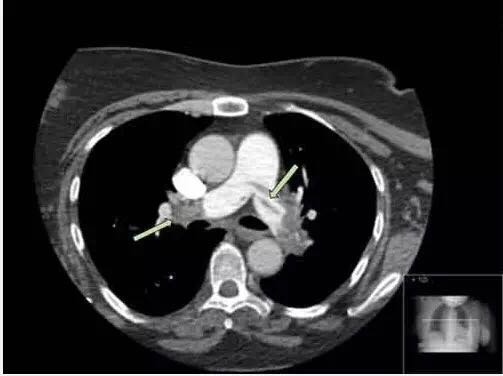

患者胸片显示左基底不透明,患者有呼吸急促加重,胸膜炎性胸痛与此诊断相符。白细胞数量增加,CRP和胸片符合肺炎的诊断。患者胸片也符合肺栓塞诊断。d-二聚体阳性符合肺栓塞诊断,同时d-二聚体升高也可见于很多感染和炎症过程。尽管患者有哮喘史,但目前没有支气管痉挛的证据。胸片不符合肺水肿诊断,同时缺少其他临床证据。胸片未出现气胸症状。患者没有任何免疫功能减弱症状或病史提示有肺孢子虫性肺炎感染风险。 入院继续完善CTPA结果:

CTPA结果显示双侧肺动脉栓塞(箭头处),左肺动脉远端几乎全部堵塞。肺血管双侧肺叶及肺段分支可见充盈缺损。 诊断:肺栓塞 本例患者我们以华法林开始抗凝治疗,持续给予低分子肝素,直到INR维持2.0-3.0。对潜在促凝血状态的患者应及时给予抗凝治疗以保证他们的生存。